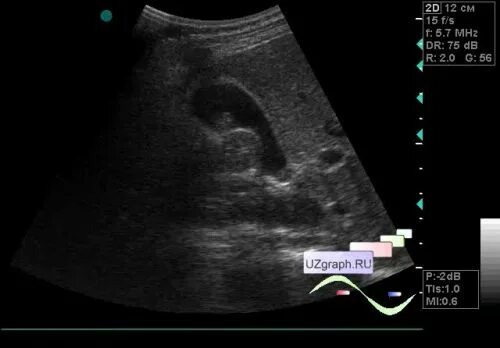

Полип желчного пузыря мкб 10 у взрослых